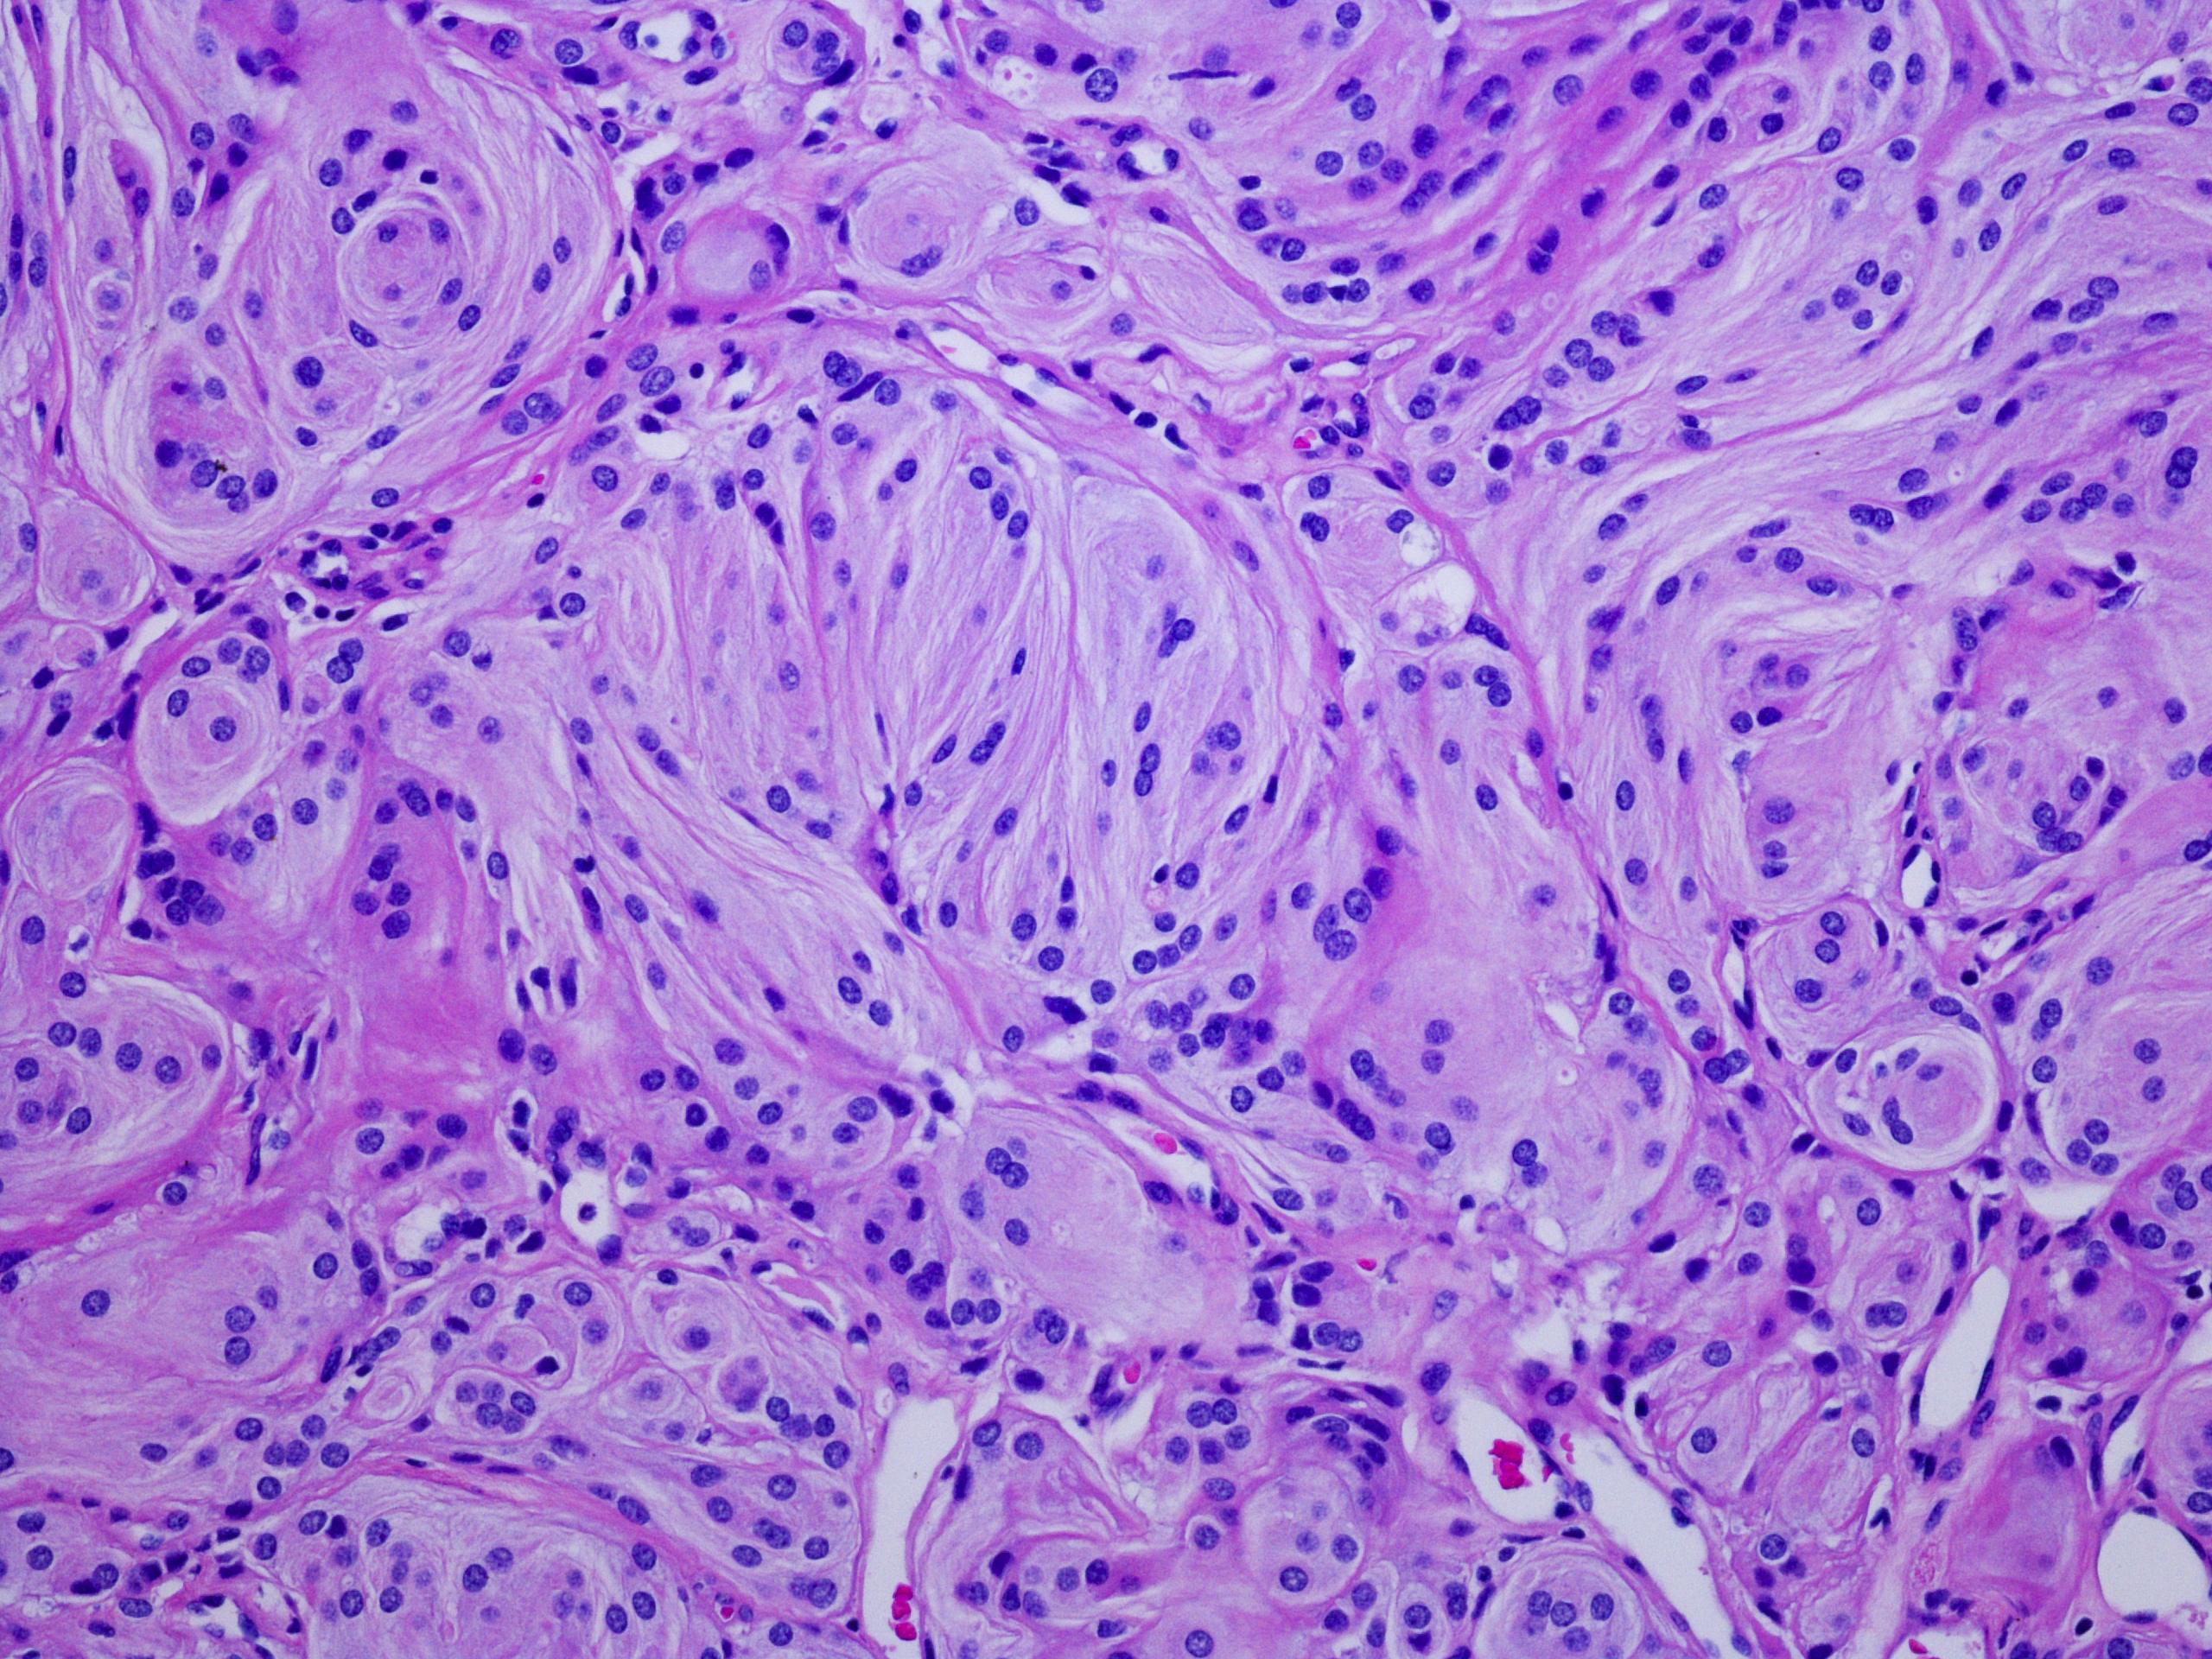

High-quality histology and staining are foundational to understanding tissue architecture, cellular behavior, and materialโ€“tissue interactions at the microscopic level. Histology & Staining Services enable detailed evaluation of biological response, biocompatibility, inflammation, integration, and structural organization across native tissues, engineered constructs, and biomaterials.

Histology reveals tissue structure, cellular organization, inflammation, fibrosis, vascularization, and biological response. Staining methodsโ€”including H&E, Masson’s Trichrome, PAS, Alcian Blue, IHC, and IFโ€”highlight essential features for evaluating biocompatibility and functional performance.

Advanced Histology and microscopy imaging analysis showing tissue morphology and biomaterial interactions.

Stained tissue section showing cellular morphology under brightfield microscopy.